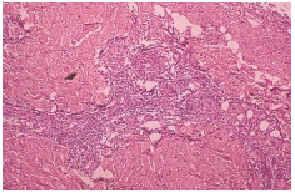

El cultivo de piel no fue relevante. El estudio histopatológico de piel mostró necrosis dermoepidérmica, y vasos congestivos y engrosados, así como la presencia de trombos en vías de resolución en pequeños vasos de la dermis (fig. 3). La inmunofluorescencia directa positiva para inmunoglobulinas, fibrinógeno y C3 en la pared de vasos de pequeño calibre de la dermis fue negativa. Una telerradiografía de tórax mostró cardiomegalia grado I y abombamiento de arco pulmonar. La gammagrafía pulmonar perfusoria con hipoperfusión leve y un ecocardiograma pone de manifiesto hipertensión pulmonar. Las pruebas de función respiratoria dieron como resultado una moderada restricción de la capacidad vital. Con estos datos se llegó al diagnóstico de hipertensión pulmonar.

Fig. 3.--Trombosis de pequeños vasos en la dermis.

Los hallazgos histopatológicos de este síndrome consisten en trombosis no inflamatorias de vasos pequeños de la dermis como hallazgo más común, que pueden acompañarse de proliferación capilar en dermis subpapilar. Los hallazgos de inmunofluorescencia directa incluyen depósitos de fibrinógeno, IgM granular y C3 en los vasos dérmicos7-11.